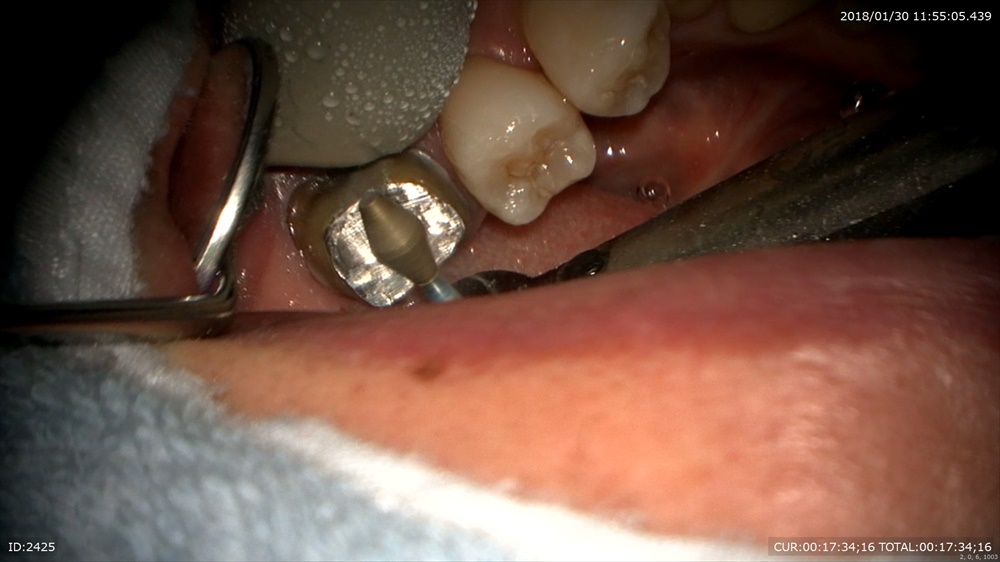

下の方のようにかぶせ物があっていないと根管内に細菌感染が起こり再発する可能性が高くなるわけです。

今日は外して感染源を除去。マイクロスコープで行うから血が一切でません。